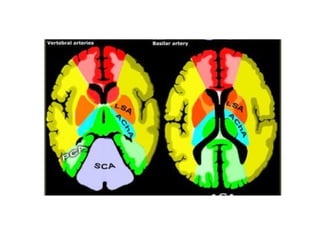

Vascular territories of the brain

Left ACA territory

Right ACA territory

Right MCA territory

Diffusion-weighted MRI of the brain showing a large-vessel

ischemic stroke of the left middle cerebral artery (MCA) territory

Left PCA territory

PICA Infarction

Sharp midline delineation

SCA territory

Right AChA territory

Right lateral lenticulostriate artery territory

Watershed zones